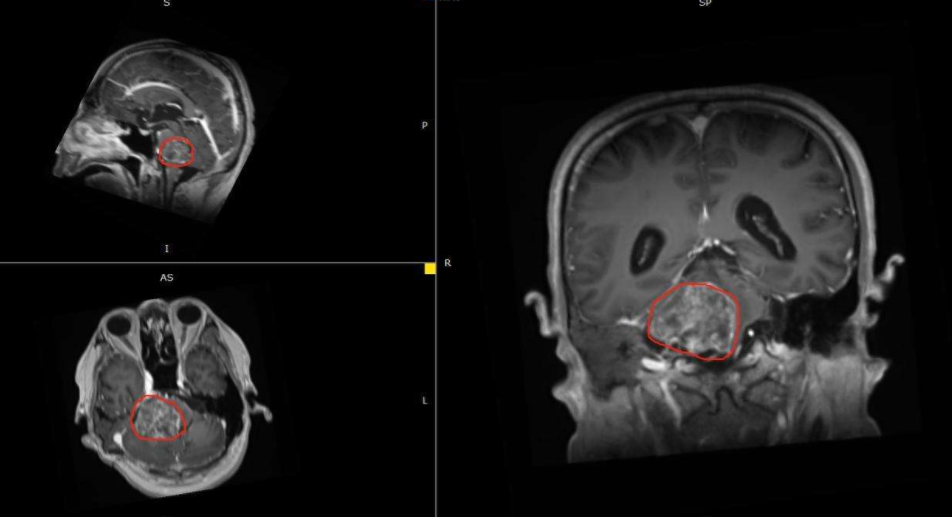

刘女士胶质瘤手术影像图: